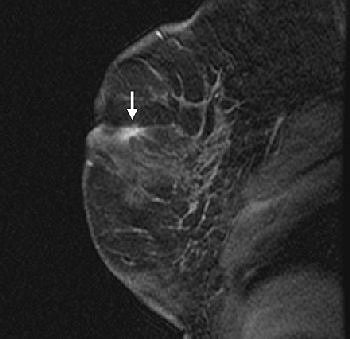

| Fifty-four-year-old woman with history of left breast cancer with normal mammogram and no palpable lumps, in whom MRI detected speculated right breast mass with no sonographic correlate. Sagittal fat-suppressed T1-weighted, contrast-enhanced scout image from MRI-guided biopsy shows 0.9 cm mass with speculated borders, irregular shape, and heterogeneous enhancement in right retroareolar region (arrow). |